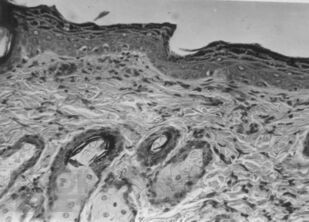

Лишай Видаля: экспериментальное и клиническое применение ультрафонофореза флюоцинолона ацетонида

Монография предназначена для врачей дерматовенерологов, физиотерапевтов, врачей общей практики, студентов выших медВУЗОВ для эффективного и обоснованного применения метода ультрафонофореза флюоцинолона ацетонида у пациентов с простым хроническим лишаем (лишаем Видаля, ограниченного или очагового нейродермита).